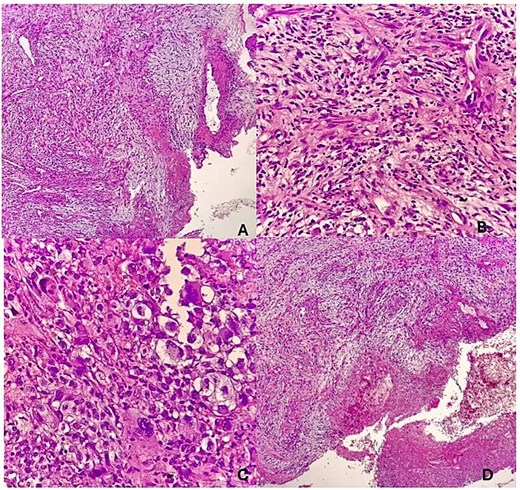

He presented to our facility with a 1-week history of spontaneous bleeding from a recurrent forehead swelling. There were associated palpitations, malaise, fever, anorexia, dizziness, and throbbing headaches. There was no altered mentation, loss of consciousness, or convulsions. On physical examination, he was alert, ill-appearing, and cachectic. He was afebrile with a pulse rate of 104 bpm and a blood pressure of 140/80 mmHg. There was moderate pallor with no lymphadenopathy, no clubbing, and no edema. There was a foul smelling, bicornuate, ulcerated forehead mass measuring 10 × 8 × 6 cm, with irregular borders. The mass was pink and friable with bleeding and areas of sloughing. It was soft with a smooth surface and no temperature gradient. There was tenderness to palpation with extension to the underlying bone (Fig. 1). A CT scan of the head was performed that demonstrated a frontal scalp mass with underlying invasion of the bone (Fig. 2).

(A) Bicornuate, ulcerated forehead mass with irregular borders. (B) The mass was friable with areas of bleeding and sloughing.